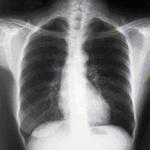

Radiografía de tórax que muestra una adenopatía hiliar bilateral en un paciente con sarcoidosis

De la colección personal del Dr. M.P. Muthiah, Departamento de Medicina Intensiva y Pulmonar y Medicina del Sueño, University of Tennessee